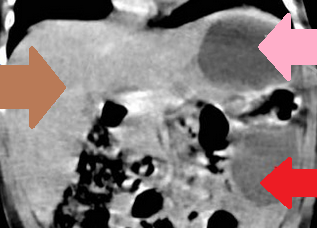

Red arrow – Wandering spleen. Pink arrow – Gastric volvulus. Brown arrow – Liver. Courtesy Dr. V. Penopoulos.